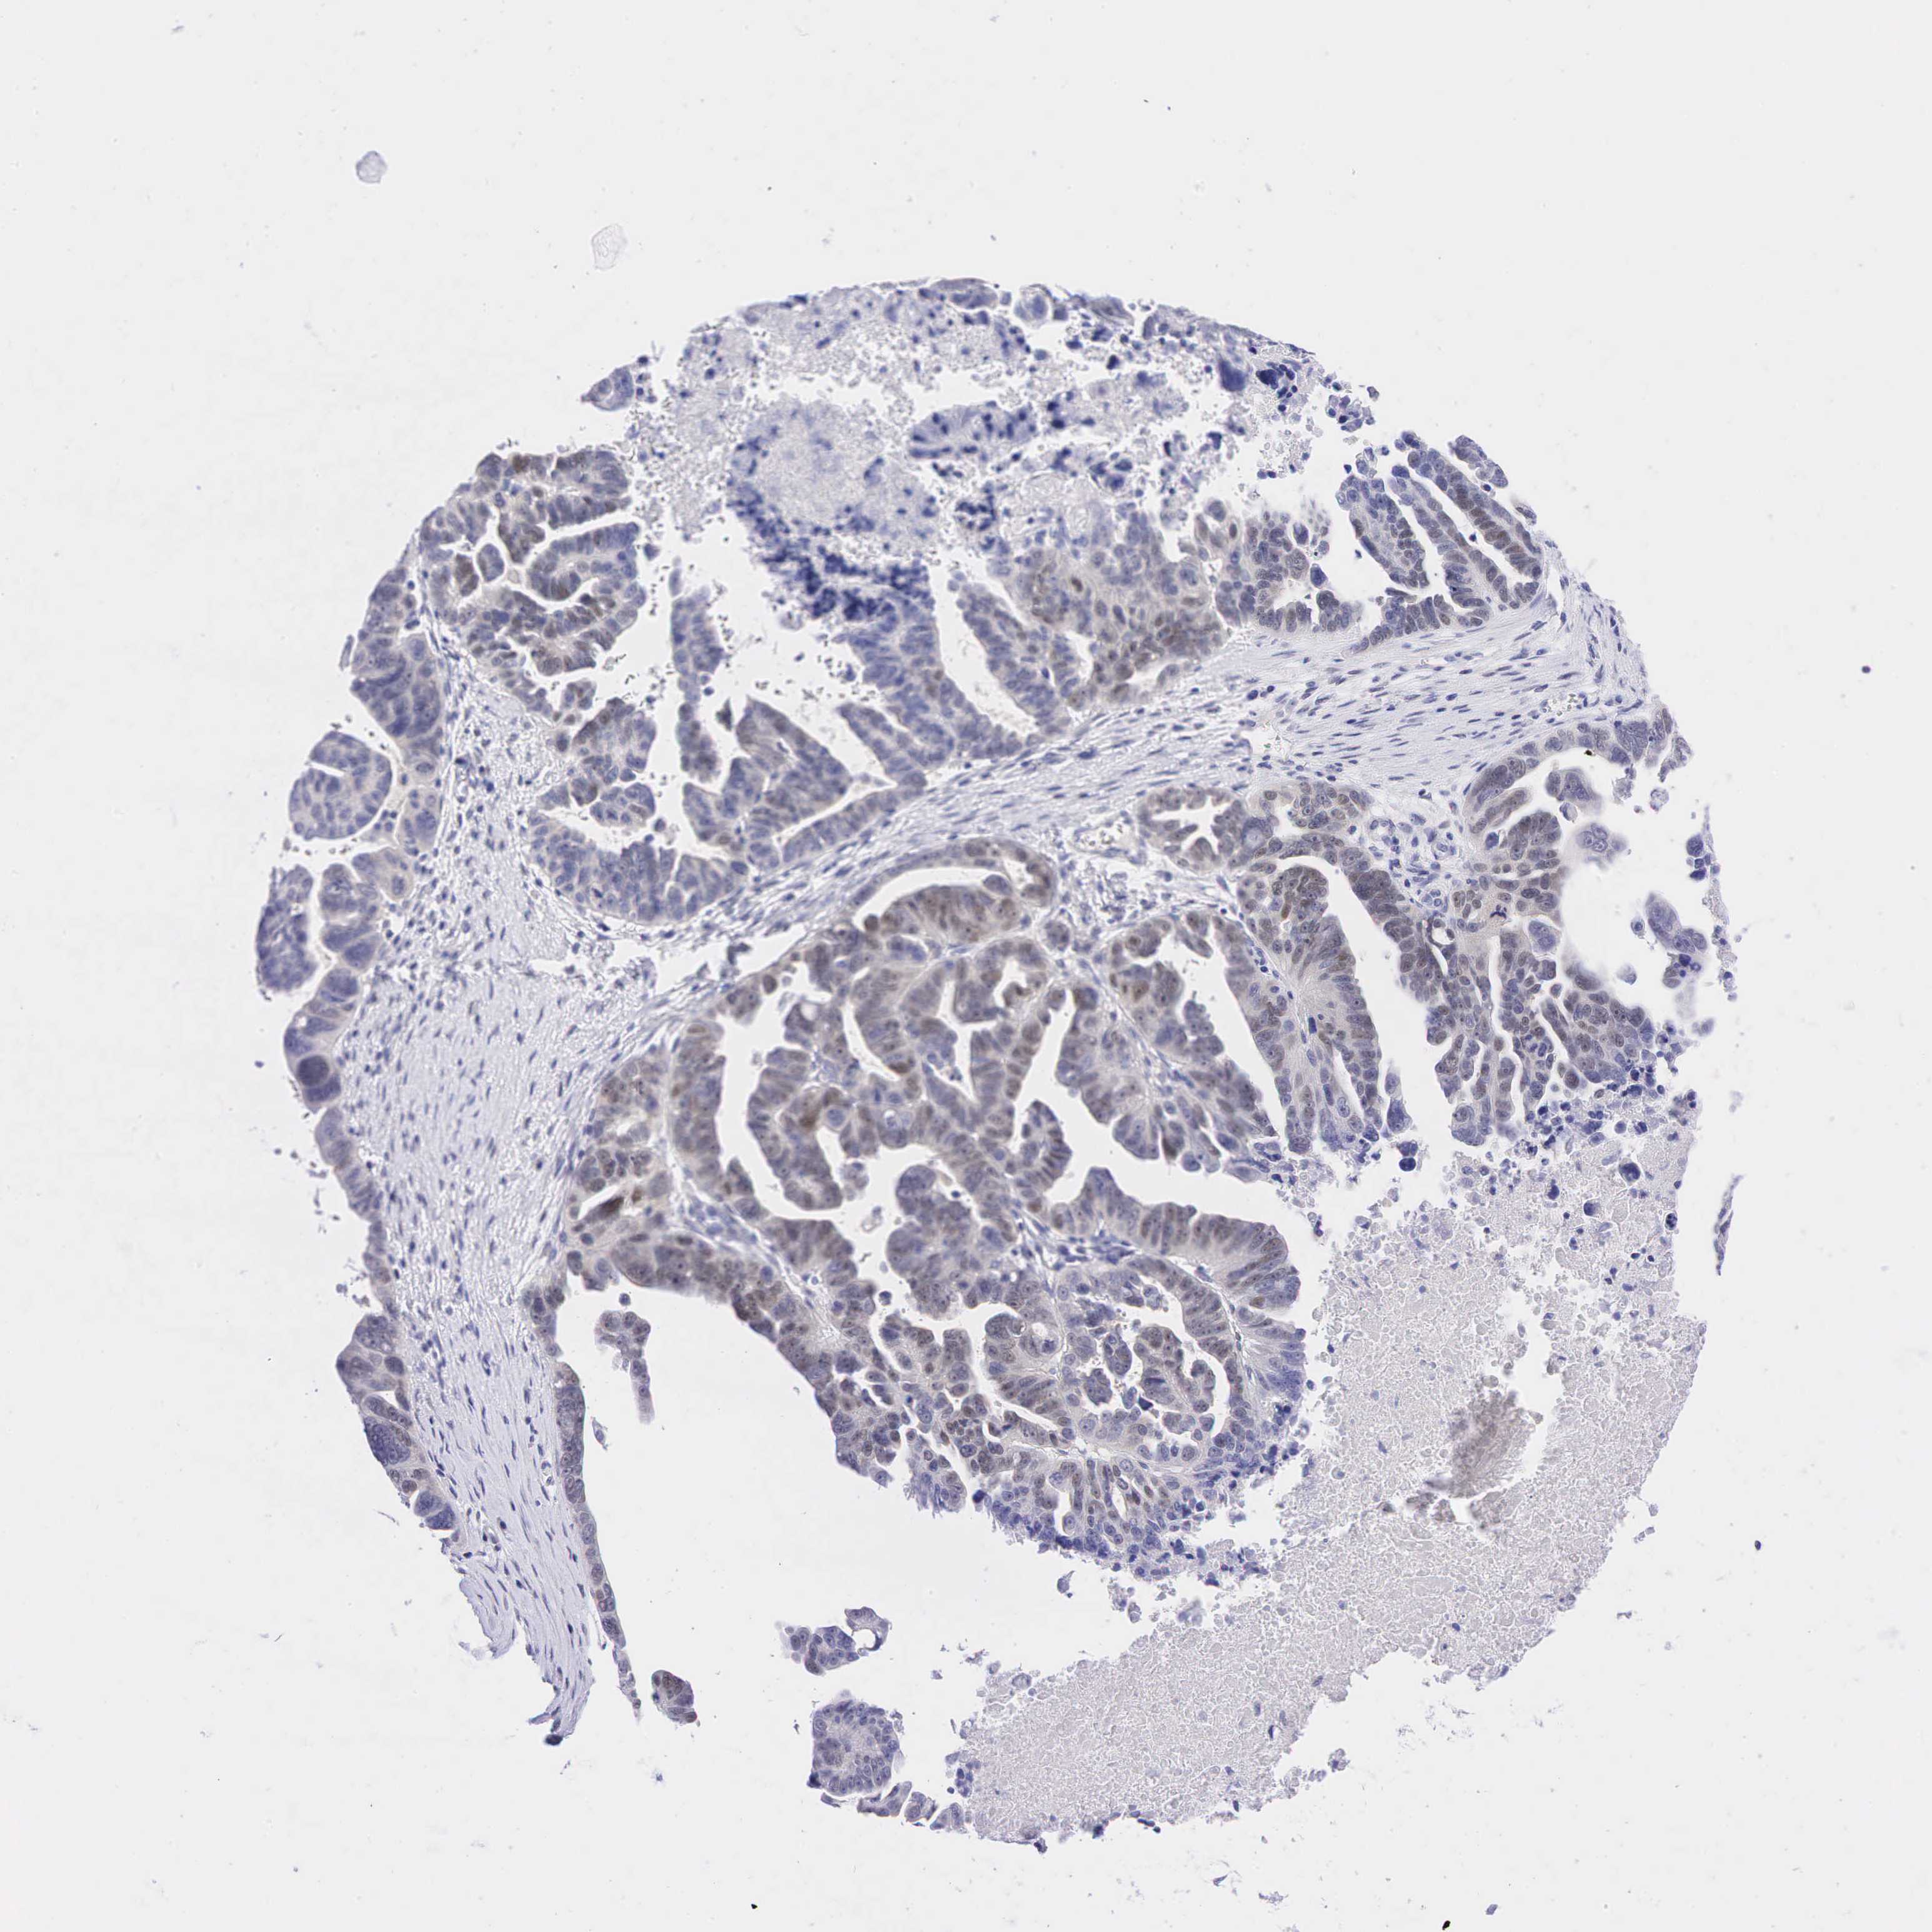

OVARIAN CANCER - Protein expressioni

A mouse-over function shows sample information and annotation data. Click on an image to view it in a full screen mode. Samples can be filtered based on level of antibody staining by selecting one or several of the following categories: high, medium, low and not detected. The assay and annotation is described here.

Note that samples used for immunohistochemistry by the Human Protein Atlas do not correspond to samples in the TCGA dataset.

Antibody stainingi

Antibody staining in the annotated cell types in the current human tissue is reported as not detected, low, medium, or high, based on conventional immunohistochemistry profiling in selected tissues. This score is based on the combination of the staining intensity and fraction of stained cells.

Each image is clickable and will lead to virtual microscopy that enables deeper exploration of all samples and also displays staining intensity scores, fraction scores and subcellular localization as well as patient and tissue information for each sample.

Antibody CAB000001

Antibody CAB065764

Staining

High

Medium

Low

Not detected

Intensity

Strong

Moderate

Weak

Negative

Quantity

>75%

75%-25%

<25%

None

Location

Nuclear

Cytoplasmic/membranous

Cytoplasmic/membranous,nuclear

Cystadenocarcinoma, mucinous, NOS

Carcinoma, endometroid

Cystadenocarcinoma, serous, NOS

Adenocarcinoma, NOS